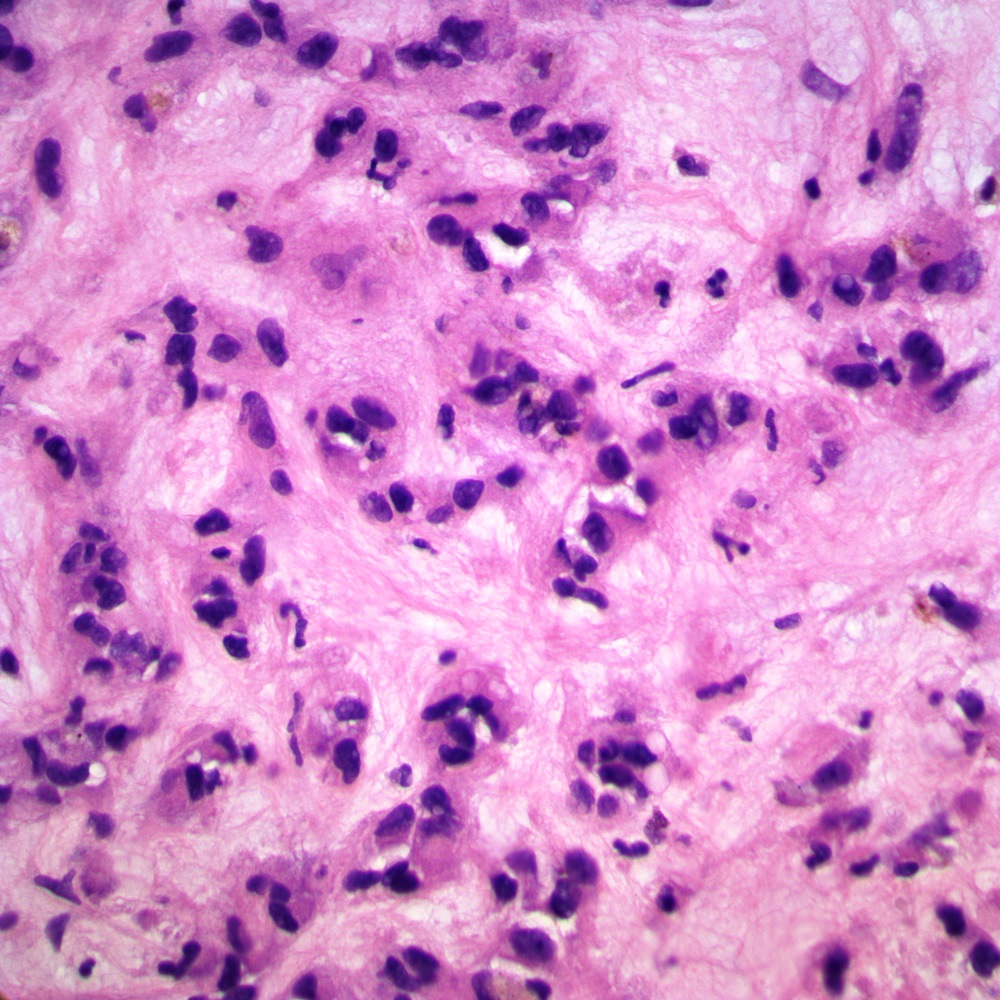

| Figure 4: 40x, 1st biopsy core. |

| Figure 5: 40x, 1st biopsy core. |

Its histologic features are quite distinctive in the liver. In hepatic EHE the tumor is often multifocal, with calcifications seen radiographically. They are firm, white to yellow, with ill-defined borders. Tumor cells are both dendritic and epithelioid in various proportions. The spindle cells are irregularly shaped and elongated. Epithelioid cells are rounder with more abundant eosinophilic cytoplasm. Small papillations or tufts of tumor cells may be seen within thin-walled vascular spaces. Abortive vascular differentiation is typically seen, with tumor cell cytoplasm containing a single vacuole representing a capillary luminal space — so-called “blister cells.” Tumor cells lie within a variably myxoid to fibrous stroma. The tumor often infiltrates hepatic vein and portal vein branches, leading to Budd-Chiari syndrome as a possible presentation. The tumor tends to grow around and leave pre-existing hepatic structures intact, particularly at the periphery of tumor nodules. In these areas, only subtle infiltration of tumor cells may be seen within sinusoids, in an otherwise architecturally normal liver, something which can be particularly treacherous in small liver biopsies.

In the second setting, the tumor is hypocellular and has a fibrotic stroma, and can closely mimic fibrosis or confluent necrosis with drop-out. In this setting, the tumor can be very difficult to diagnose on limited core biopsy material. One can look for focal areas of greater cytologic atypia, or areas of sinusoidal infiltration of tumor cells. A vascular IHC stain can be helpful to highlight such infiltration, keeping in mind not to misinterpret capillarization of sinusoids, which can be seen in various settings.